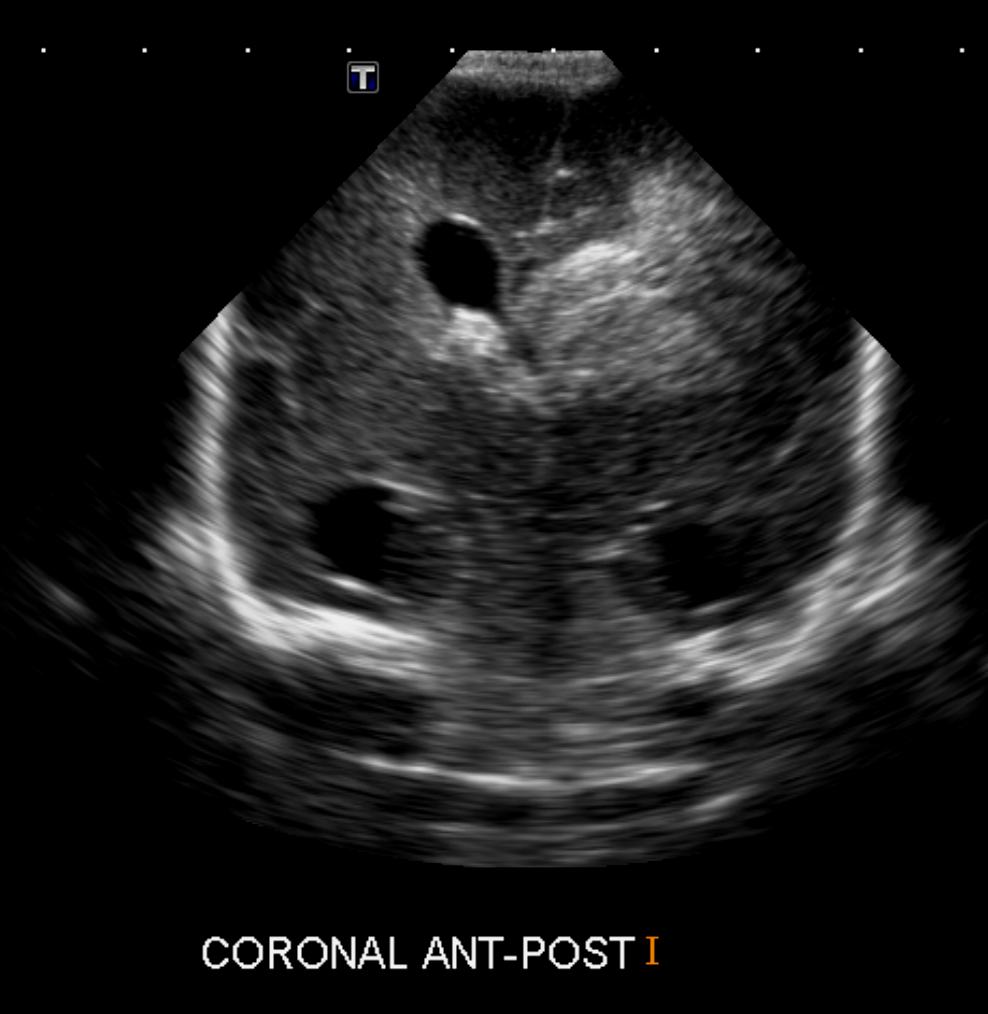

Info Images Findings Impression Reco/Acuity Case Images View Images / Launch Visage Case Notes History Full term infant. We are asked to evaluate posterior fossa cyst. Exam Gray scale and Doppler Ultrasonographic examination of the head. Prior Study N/A Dicom View Reference Material

Section 1 Submit Findings Case149 Findings Brain The brain is immature. Yes No There is under-sulcation and open sylvian fissures. Yes No There is/are multiple hypoechoic areas in the periventricular white matter. Yes No There is/are multiple hyperechoic areas in the periventricular white matter. Yes No There is diffuse cerebral edema with diffusely increased echogenicity of the brain parenchyma and loss of grey white matter differentiation. Yes No The thalami/basal ganglia are hypoechoic. Yes No There is periventricular calcification. Yes No There is intra-parenchymal calcification. Yes No CSF spaces/ventricular system There is a prominence of the extra axial fluid spaces. Yes No There are debris/septations in the extra axial fluid spaces. Yes No There are debris/septations in the ventricles. Yes No There is a subdural collection on the right/left side. Yes No There is prominence of the ventricular system. Yes No There is an asymmetry of the ventricular system. Yes No There is a cavum septum pellucidum. Yes No There is a midline shift towards right/left. Yes No The choroid plexus is bulky/lobulated. Yes No There is a choroid plexus cyst measuring… Yes No There are debris/clots in the occipital horn. Yes No There is a posterior fossa cyst measuring… Yes No The tentorium is elevated/depressed. Yes No The lateral ventricle/s are dilated. Yes No The third ventricle is dilated. Yes No The 4th ventricle is dilated. Yes No There are pseudo cysts. Yes No Germinal matrix hemorrhage (Only in the premature infants): Please do not answer if the patient is a full term. There is a germinal matrix hemorrhage, consistent with a grade I hemorrhage. Yes No There is an intraventricular extension consistent with a grade II hemorrhage. Yes No There is an intraventricular extension with the dilatation of ventricles, consistent with a grade III hemorrhage. Yes No There is an intra-parenchymal extension, consistent with grade IV hemorrhage. Yes No On color Doppler examination, the Resistive index in the anterior cerebral artery is… There is a loss of the diastolic flow on the Doppler exam. Yes No There is altered vascularity on Doppler imaging. Yes No There is an AVM in the region of… Yes No